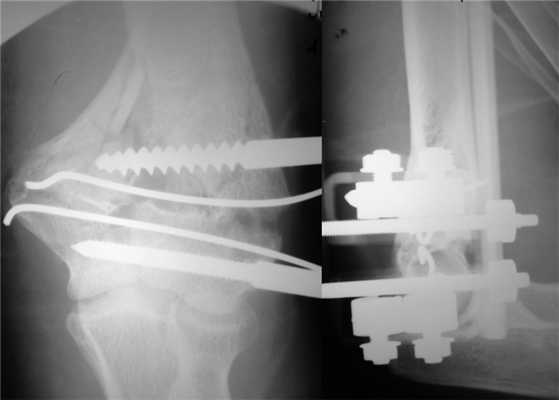

На следующий день под новокаиновым блоком плечевого сплетения произведена операция: закрытая репозиция и чрескостный остеосинтез левой плечевой кости спице-стержневым аппаратом внешней фиксации конструкции А.И. Городниченко. Через разрезы кожи и мягких тканей по наружной поверхности левого плеча длиной до 5 мм введено 2 кортикальных стержня в диафиз плечевой кости, один кортикальный и один спонгиозный стержень и 2 спицы с упорной площадкой в мыщелки и надмыщелки плечевой кости. После фиксации проксимальных стержней в аппарате под контролем электронно-оптического преобразователя произведена закрытая репозиция с помощью съемных рукояток с последующей стабилизацией дистальных стержней и спиц (рис. 3). Рисунок 3. Рентгенограммы больной П. после остеосинтеза левой плечевой кости спице-стержневым аппаратом. Кожа вокруг стержней ушита одиночными швами. Кровопотеря в ходе операции 20 мл. Продолжительность операции 40 мин.